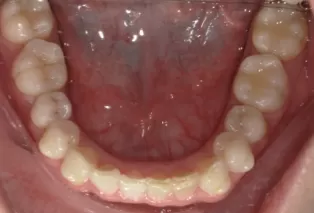

Photos intra-orales